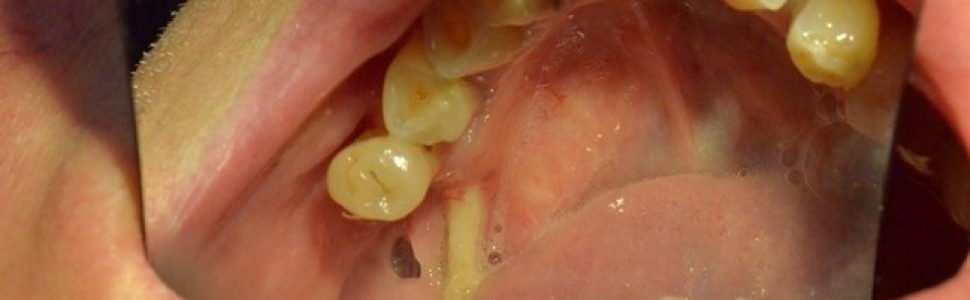

Jeżeli rozpozna się martwicę kości szczękowych, należy pacjenta skierować do poradni chirurgii stomatologicznej lub szczękowo-twarzowej, gdzie otrzyma on niezbędną pomoc (ryc. 1) (8, 9).

Ryc. 1. BRONJ w żuchwie – stan po usunięciu zęba 46 (obraz w lusterku).